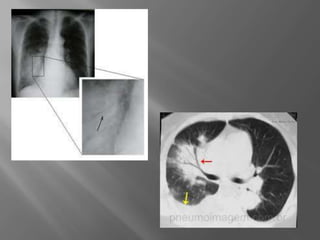

 Diagnóstico:

 Rx de Tórax;

 TC de tórax;

 Broncoscopia;

 Biópsia ( pulmonar,pleural, ganglionar).

 Diagnóstico:  Rxde Tórax;  TC de tórax;  Broncoscopia;  Biópsia ( pulmonar,pleural, ganglionar).